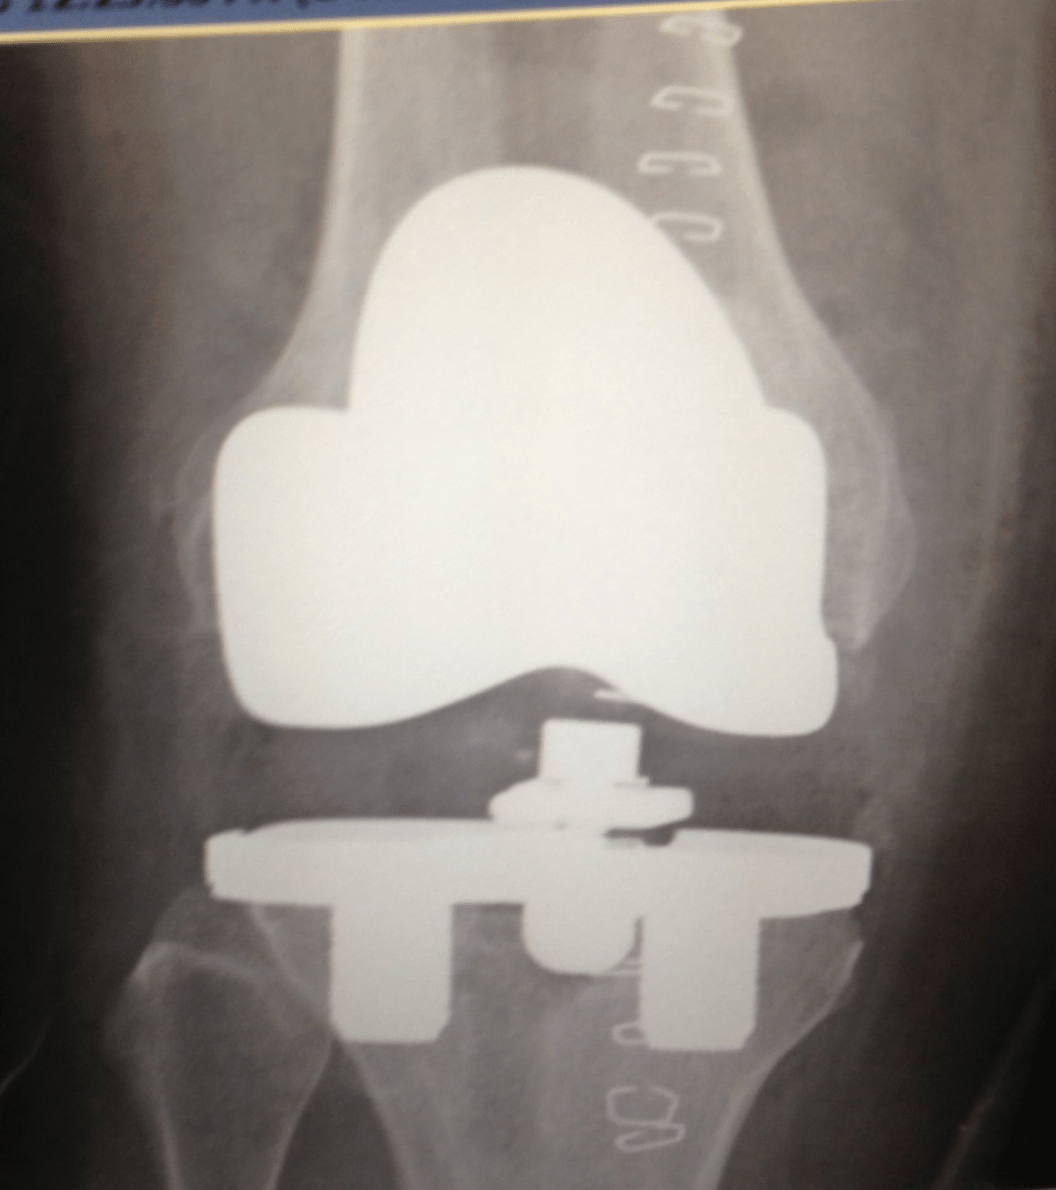

Postoperative plain radiographs after revision total knee

Postoperative plain radiographs after revision total knee Total Knee Replacement Zimmer Nexgen The surgeon when implanting the nexgen cr total knee prostheses. Patient specific instruments ct, complete knee solution. The surgeon should choose the preferred instrumentation system preoperatively. Zimmer biomet offers surgeons total knee systems, partial knee systems, bicruciate preserving arthroplasty systems and revision knee systems. The principal goals of primary total knee arthroplasty are reestablishment of normal lower extremity alignment, proper. Total Knee Replacement Zimmer Nexgen.